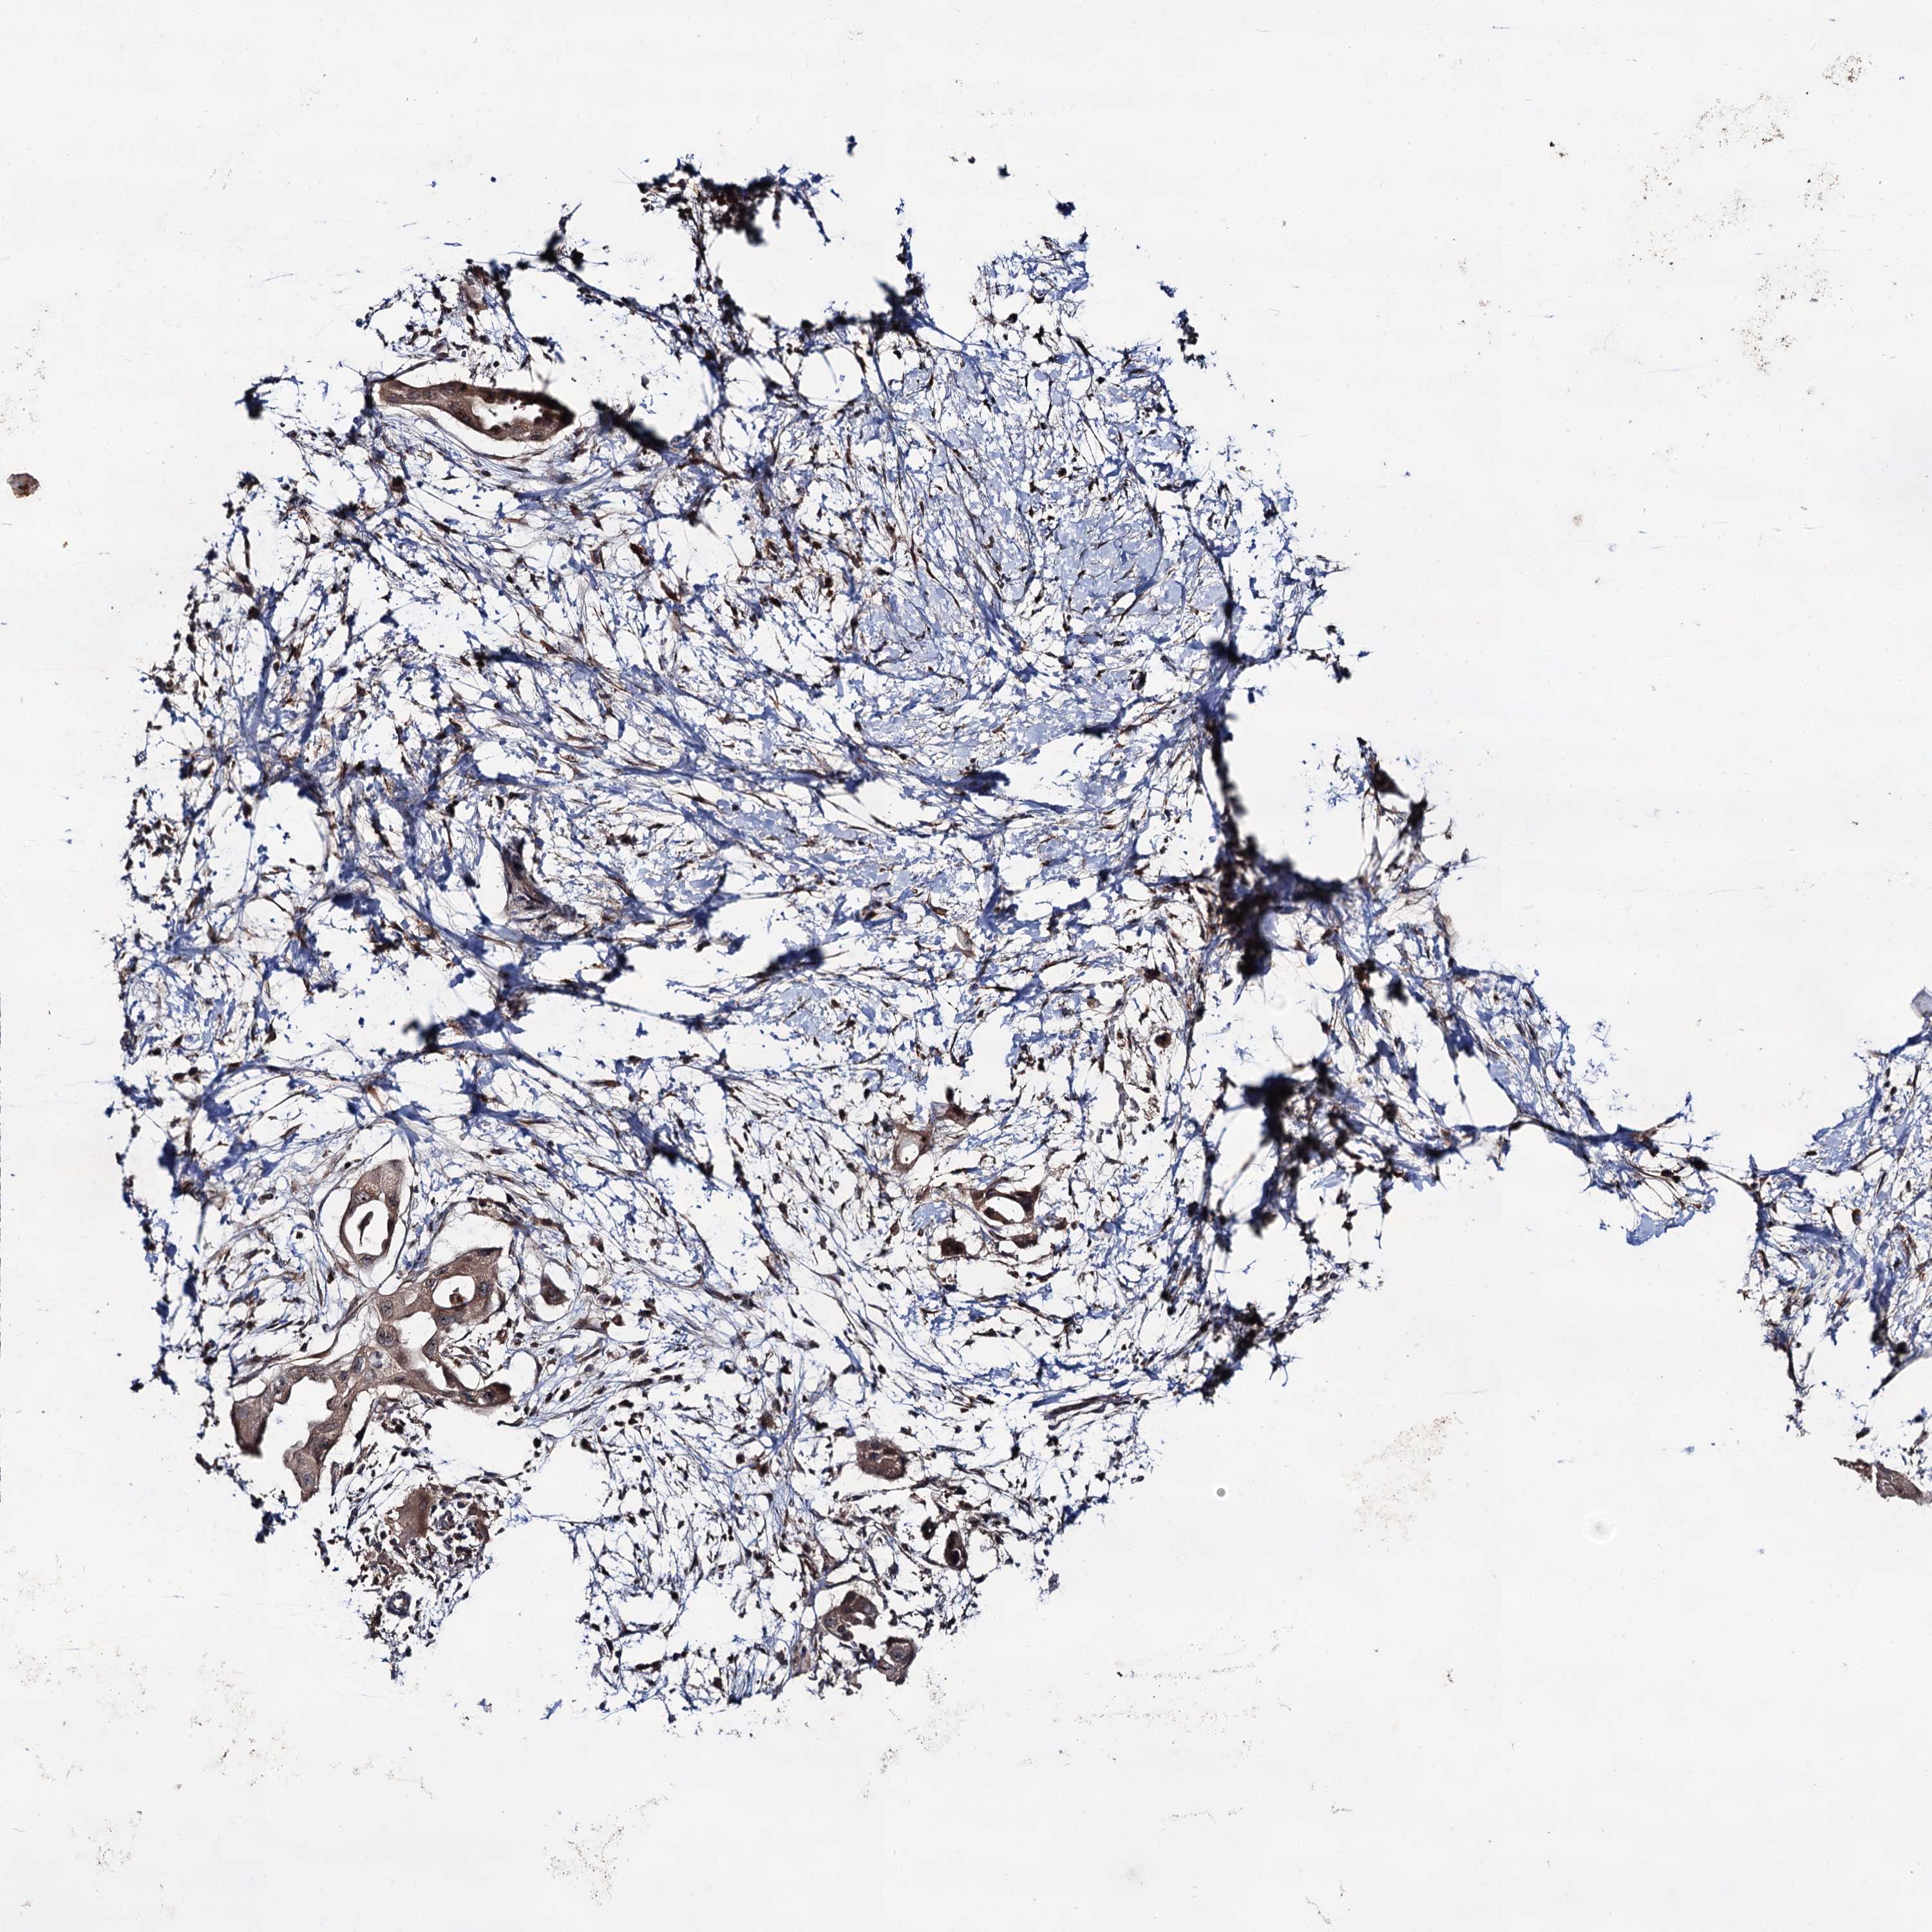

PANCREATIC CANCER - Protein expressioni

A mouse-over function shows sample information and annotation data. Click on an image to view it in a full screen mode. Samples can be filtered based on level of antibody staining by selecting one or several of the following categories: high, medium, low and not detected. The assay and annotation is described here.

Note that samples used for immunohistochemistry by the Human Protein Atlas do not correspond to samples in the TCGA dataset.

Antibody stainingi

Antibody staining in the annotated cell types in the current human tissue is reported as not detected, low, medium, or high, based on conventional immunohistochemistry profiling in selected tissues. This score is based on the combination of the staining intensity and fraction of stained cells.

Each image is clickable and will lead to virtual microscopy that enables deeper exploration of all samples and also displays staining intensity scores, fraction scores and subcellular localization as well as patient and tissue information for each sample.

Antibody HPA039318

Antibody HPA039763

Adenocarcinoma, NOS